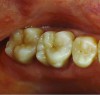

Fig 1. Preoperative (Fig 1), preparation (Fig 2), and final (Fig 3) postoperative images of a two-unit CL-I feldspathic veneer case.

Figure 1

Fig 2. Preoperative (Fig 1), preparation (Fig 2), and final (Fig 3) postoperative images of a two-unit CL-I feldspathic veneer case.

Figure 2

Fig 3. Preoperative (Fig 1), preparation (Fig 2), and final (Fig 3) postoperative images of a two-unit CL-I feldspathic veneer case.

Figure 3